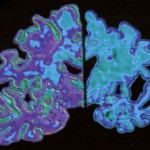

Schizofrenia: identificati nuovi percorsi tra le cause

Un nuovo studio di associazione genome-wide (GWAS) ha individuato nuovi percorsi tra le cause della schizofrenia..

In particolare, lo studio individua 22 sedi, di cui 13 che sono di recente scoperta, che hanno un ruolo nello sviluppo della schizofrenia.